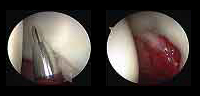

Arthroscopy provides a good way to address problems within the hip joint with less tissue damage and faster recovery and comfort.

La artroscopia es un procedimiento quirúrgico que permite estudiar, diagnosticar y tratar problemas en una articulación. Consiste en la introducción por punción, en este caso dentro de la cadera, de un sistema óptico con fuente de luz conectado a una cámara digital que permite visualizar las estructuras intraarticulares. - ¿Cuáles son las lesiones más frecuentes que trata la artroscopia de cadera?